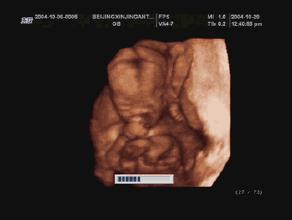

3是不是做彩超比黑白B超好?

彩超即是清晰度更高的黑白B超,同时还能提供血流动力学信息,会用彩色标注心脏、血流等指标,能够发现血液异常,更加精准地排查胎儿畸形方面的问题。所以彩超更优于B超。